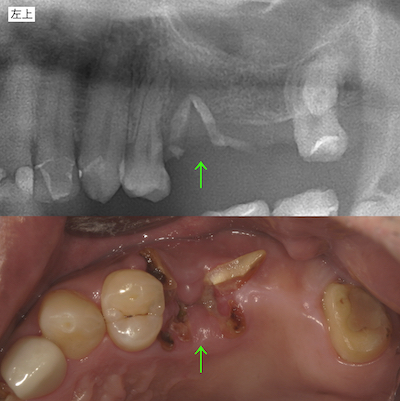

次に左上です。破折した根の周りに不良肉芽組織があるため、抜歯後に歯槽堤が安定しないことが想定されました。咬み合わせを確保する前に、骨組織再生処置を行い、組織を正常な状態に戻す事が必要であることを説明しました。

右上のアンカースクリューによる圧下の結果のレントゲンです。